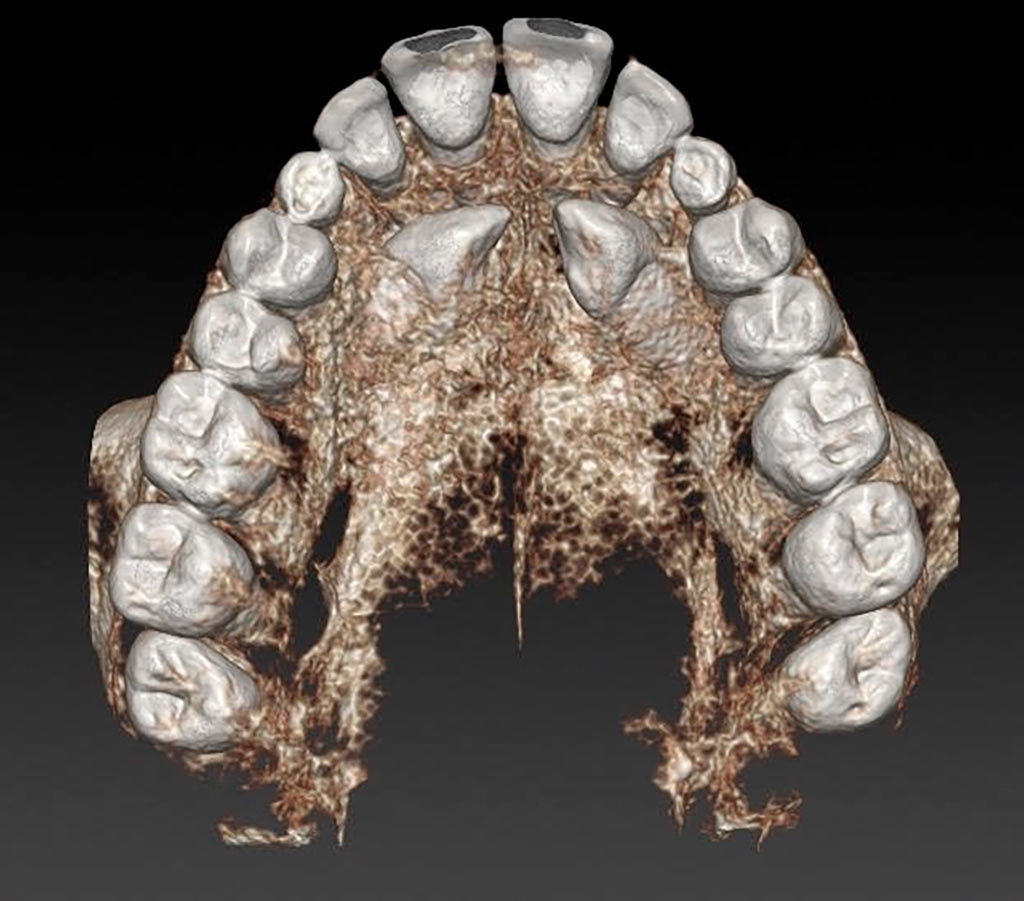

Tracción de canino con k9